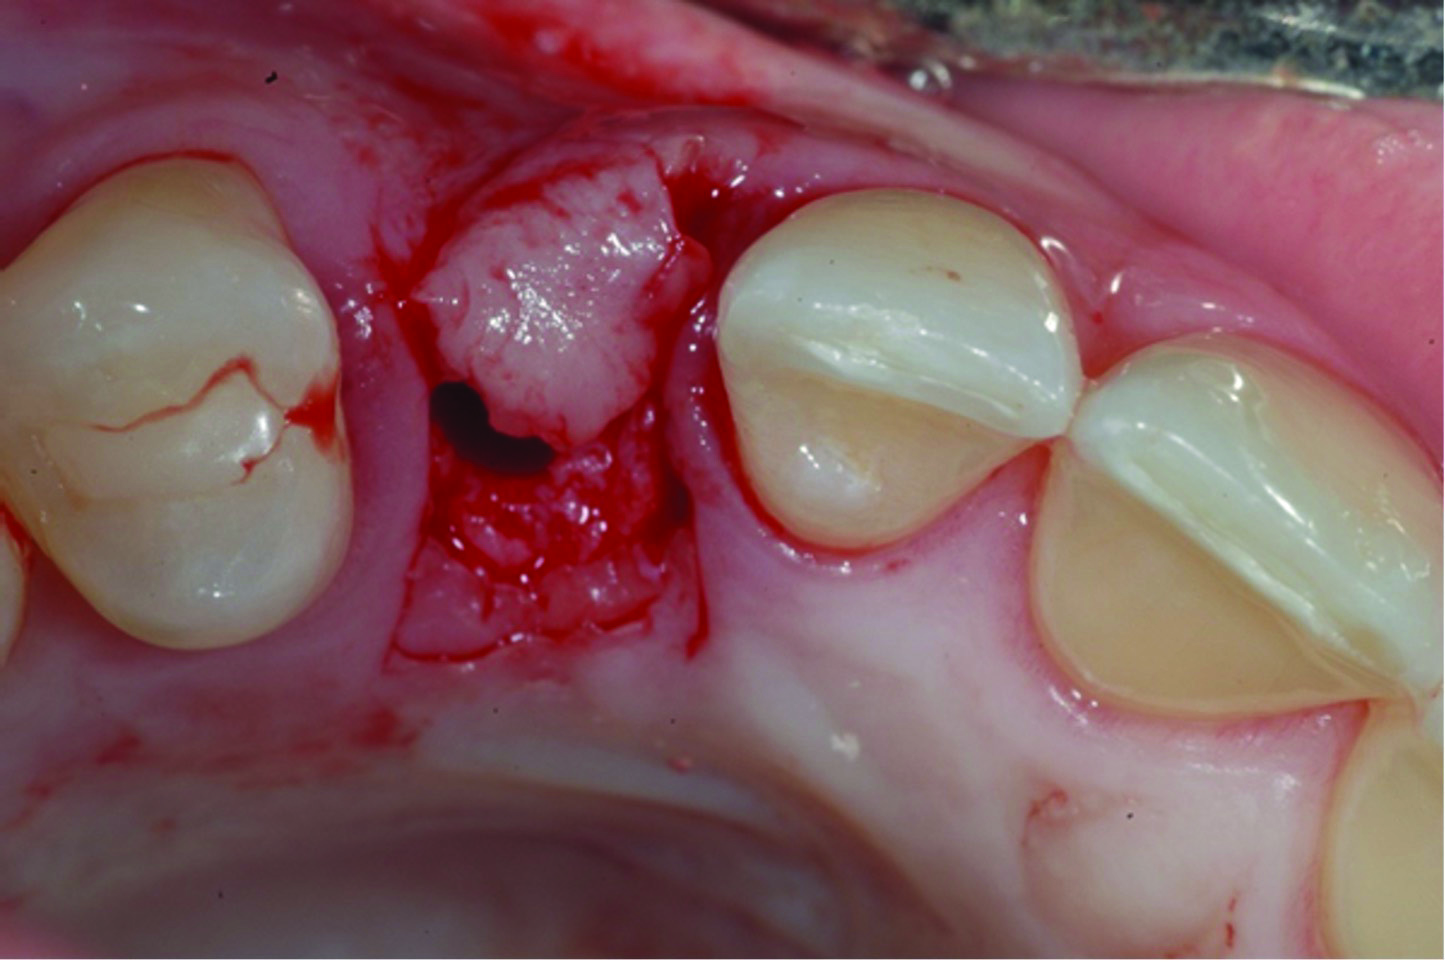

Fig 9: initial presentation;

Fig 10: healing abutment placement with FGG; Fig 11: 2 months post-treatment.

Fig 11: 2 months post-treatment.